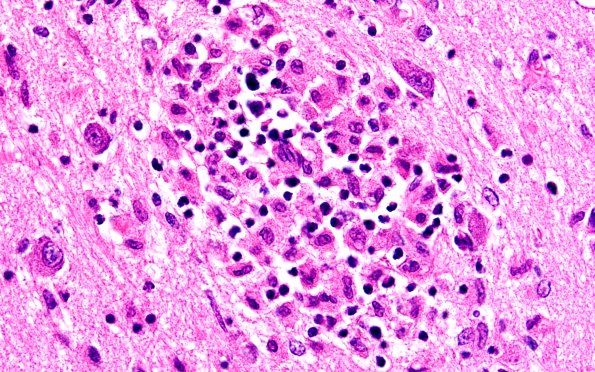

Washington University Experience | MISCELLANEOUS | Familial erythrophagic lymphohistiocytosis | 4B7 Lymphohistiocytosis (Case 4) H&E N3 60X

Higher magnification of the infiltrate demonstrates a number of inflammatory cell types including lymphocytes and impressive numbers of histiocytes. (H&E)